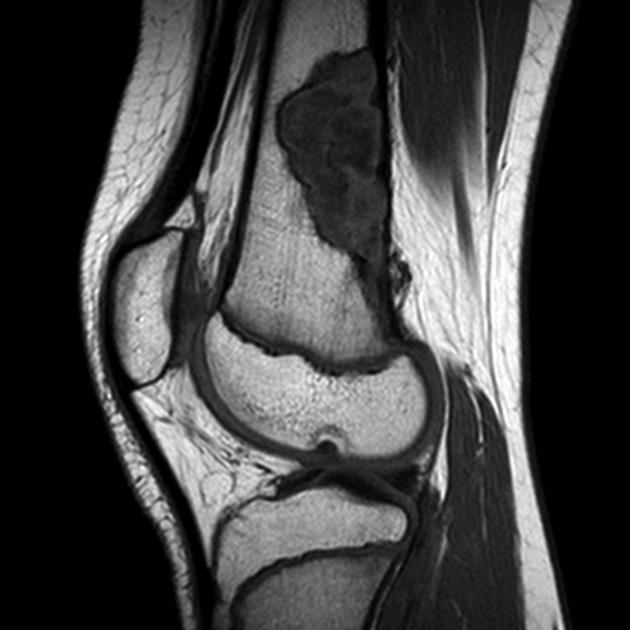

Diagnosis and sign?

AVN.

The “double line sign” is frequently seen on T2 weighted images in AVN (and bone infarcts) due to an inner bright line of granulation tissue next to an outer dark line of sclerotic bone.